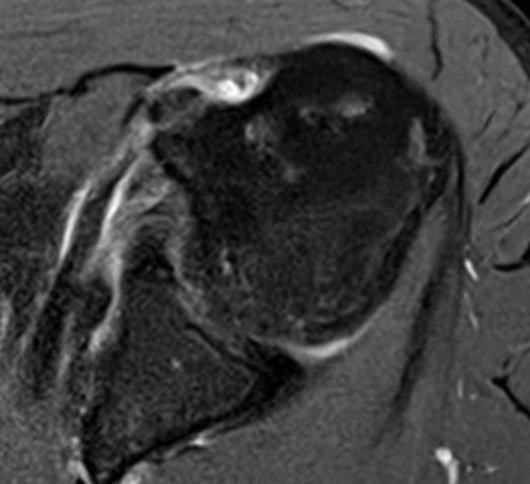

Full thickness retracted subscapularis tear

Full thickness retracted subscapularis tear with medial dislocation of long head of biceps tendon